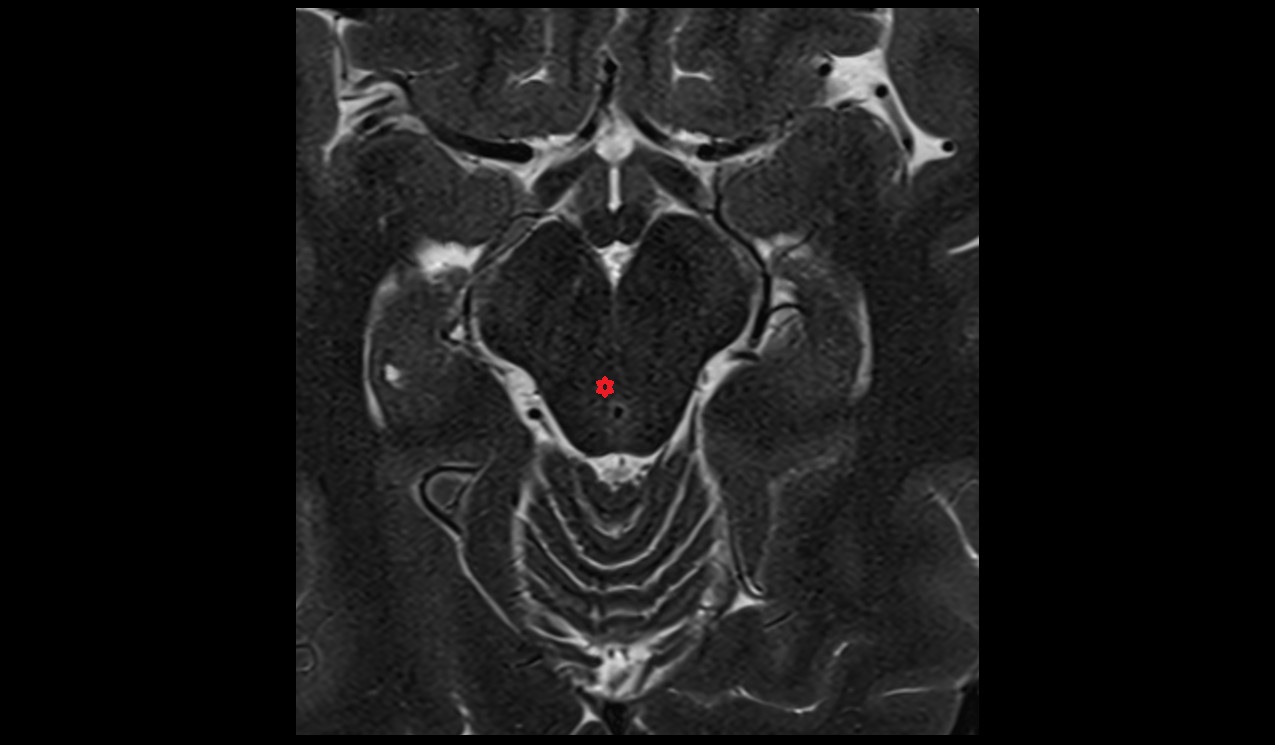

- Hippocampus

- Body of hippocampus

- Head of hippocampus

- Tail of hippocampus